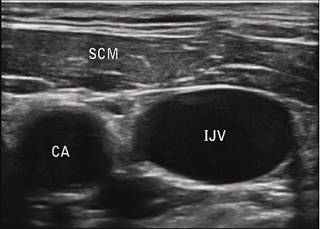

O transdutor ideal deve possuir alta resolução (alta frequência e pequeno comprimento de onda), o que possibilitará a fácil identificação de veias e artérias. Nestes casos recomenda-se o transdutor linear 7.5 a 10 MHz (3,6). Nas imagens os vasos sanguíneos aparecem como imagens tubulares anecóicas (em preto) devido à transmissão completa das ondas de ultrassom, enquanto o tecido ao redor aparece com diferentes escalas de cinza (Figura 1). As artérias são pulsáteis e não compressíveis com o transdutor, já as veias possuem válvulas e têm paredes mais finas, não são pulsáteis, são facilmente compressíveis e se distendem quando o paciente realiza uma manobra de Valsalva (3-6).

Figura 1: Corte transversal e longitudinal. A veia é demostrada pela seta e estrela vermelhas, enquanto a artéria pela seta e estrela azuis. Observe como a veia pode ser comprimida pelo transdutor (3).